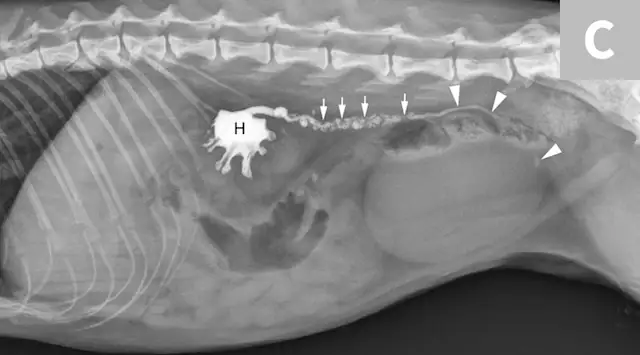

Differentiation between a complete vs partial ureteral obstruction can be difficult with survey radiography and ultrasonography alone. Antegrade pyelography (nephropyelocentesis with renal pelvic injection of iodinated positive contrast medium using ultrasound guidance) may be useful for documenting a complete vs partial obstruction (Figure 7).11

1 / 3

Lateral abdominal radiograph of a cat with multiple, small, oval mineral opacities superimposed over the ventral aspect of the retroperitoneal space (arrows). These mineral opacities are arranged linearly extending from the caudal aspect of the kidneys to the level of the urinary bladder.

Antegrade pyelography is beneficial when compared with standard IV urography, as it lowers the risk of potential contrast-induced renal damage and provides excellent filling of the renal collecting system, regardless of renal function.11